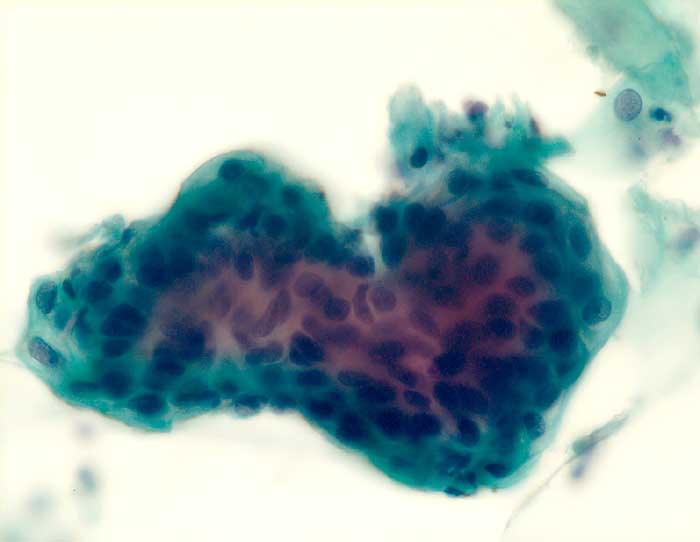

PathoPic – image database / PathoPic ID 6071 - Endometrium

Endometrium

Normalbefund

Portio

Portio: Endometriumzellverband

Postmenopausenblutung

Zytologie

500